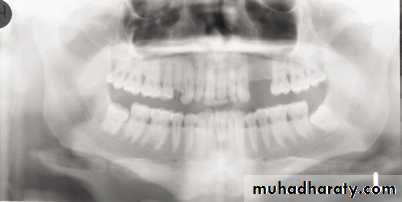

In a good panoramic radiograph:

The mandible is “U” shaped.The condyles are positioned about equal distance from the inside edges of the image and 1⁄3 of the way down from the top edge of the image.

The occlusal plane exhibits a slight curve or “smile line,” upwards.

The roots of the maxillary and mandibular anterior teeth are readily visible with minimal distortion.

Magnification is equal on both sides of the midline.

1, Mandibular condyle. 2, Articular eminence. 3, Coronoid process of mandible superimposed on zygomatic arch. 4, Posterior wall of maxillary sinus. 5, Posterior wall of zygomatic process of maxilla. 6, Hard palate. 7, Nasal septum. 8, Tip of nose. 9, Dorsum of tongue. 10, Hyoid superimposed over inferior border of mandible. 11, Inferior border of maxillary sinus. 12, Image of cervical spine. 13, Medial border of maxillary sinus. 14, Infraorbital canal. 15, Infraorbital rim. 16, Pterygomaxillary fissure. 17, Anterior border of the pterygoid plates. 18, Lateral pterygoid plate superimposed over soft palate and coronoid process of mandible. 19, Ear lobe. 20, Inferior border of mandibular canal. 21, Mental foramen. 22, Posterior wall of nasopharynx. 23, Inferior border of mandible superimposed from opposite side. 24, Soft palate over mandibular foramen of mandible.